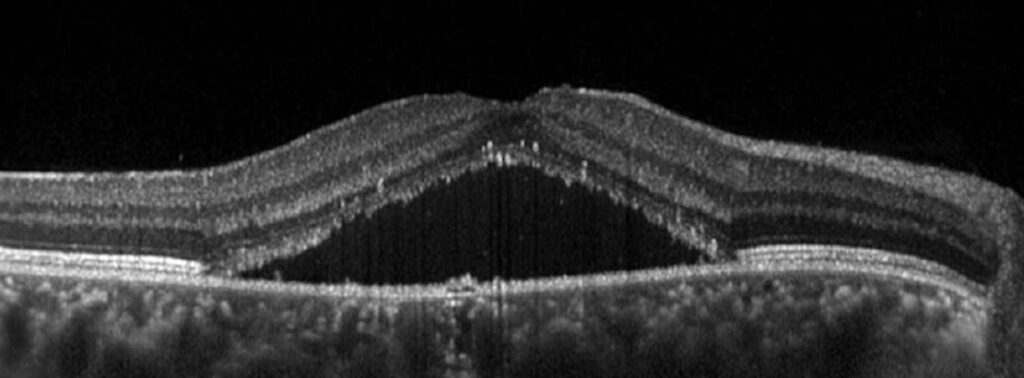

- OCT: rappresenta il gold standard diagnostico. È un esame rapido, non invasivo ed indolore che ricostruisce in 3D la retina centrale, mostrando con precisione la quantità e l’estensione del liquido sottoretinico

Dopo la diagnosi di corioretinopatia sierosa centrale, il paziente deve essere seguito con OCT periodici, ogni 3 mesi nelle fasi iniziali ed ogni 6-12 mesi quando la situazione si è stabilizzata. Questi controlli permettono di monitorare il riassorbimento del liquido e di individuare subito eventuali recidive o complicanze.